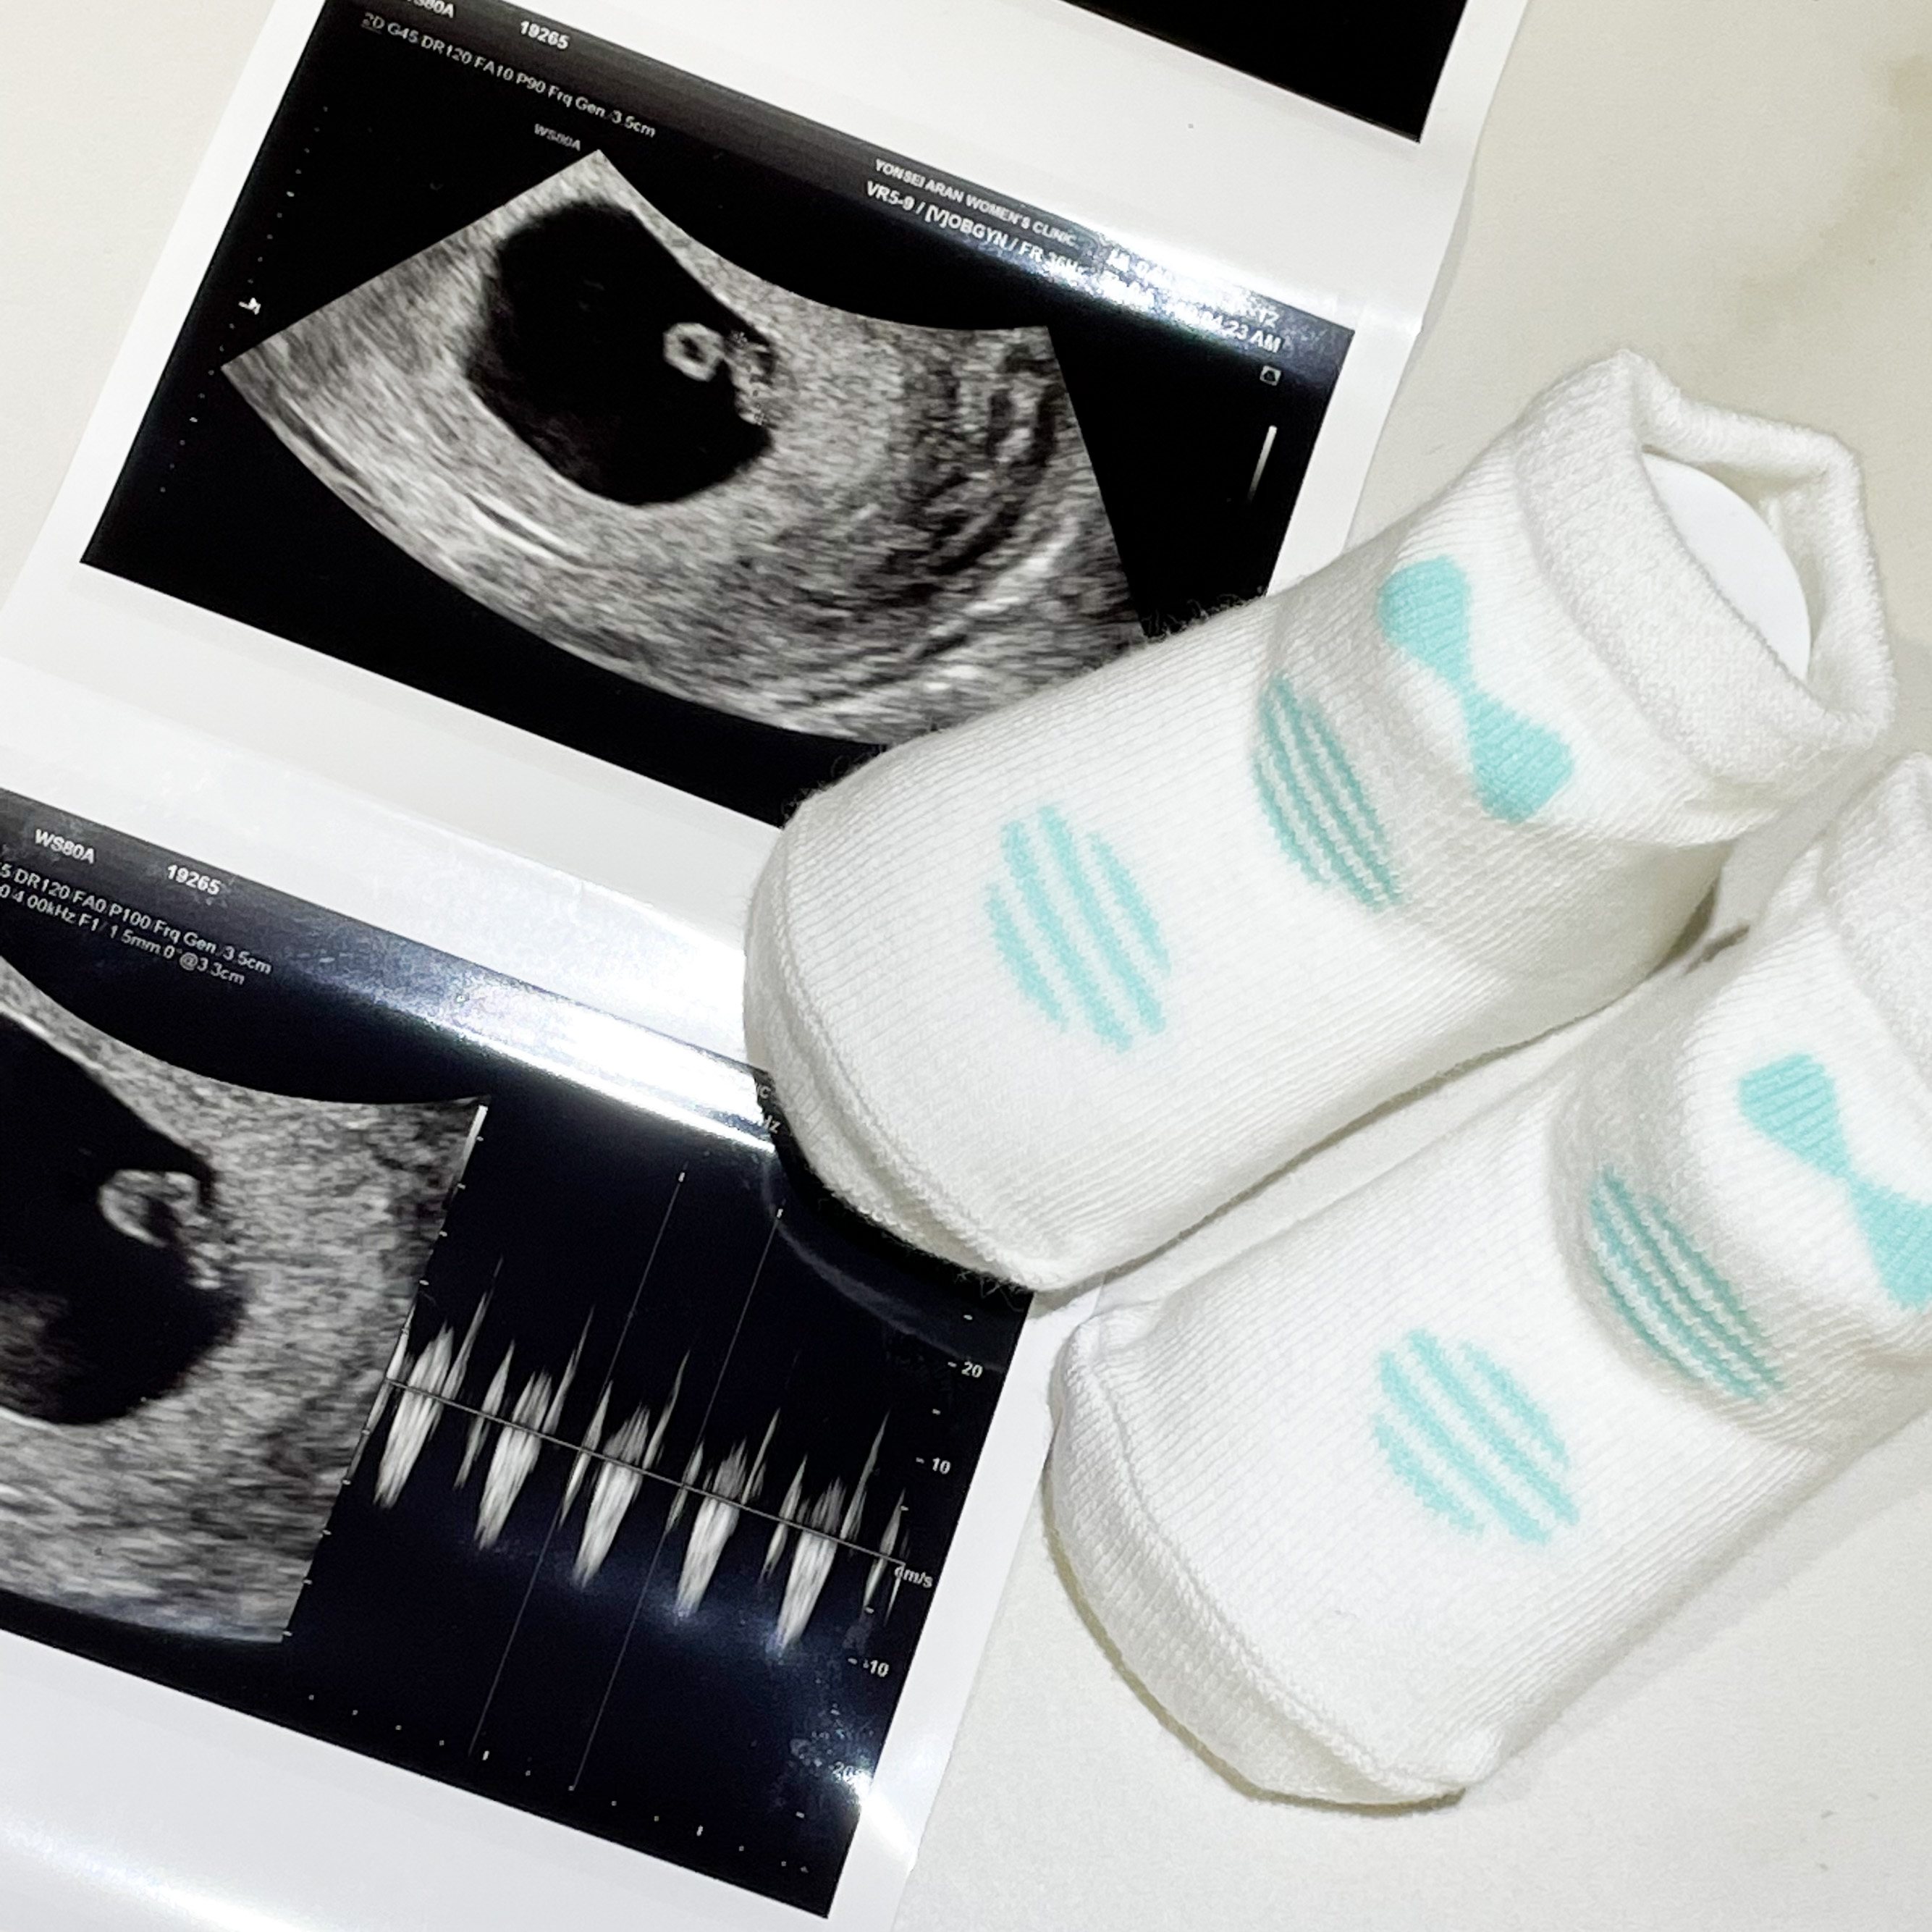

6주 4일

2주 전에는 아기집 밖에 안보였는데

이번에는 심장박동도 들을 수 있었다.

애기에 난황에 심장소리까지!!

2주동안 정말 많이 컸다.

동그라미가 머리인가 싶었는데

그게 난황이고 막대기가 애기라고 하셨다.

0.68 cm로 1 cm도 안된 아주쪼고미였다.

심장박동은 124bpm으로 아주 우렁찼다.

1cm도 안되는게 심장이 이렇게 우렁차다니 신기할 따름이었다.